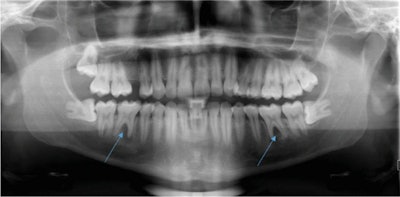

An x-ray taken in January 2020 shows apical and interradicular osteolysis on tooth #36 and #46.When the attending dentist of the university hospital explicitly asked the patient what his life was like during the periods of pain, the patient confirmed experiencing a lot of stress due to the completion of his studies, as well as pressing his teeth at night, according to the report.